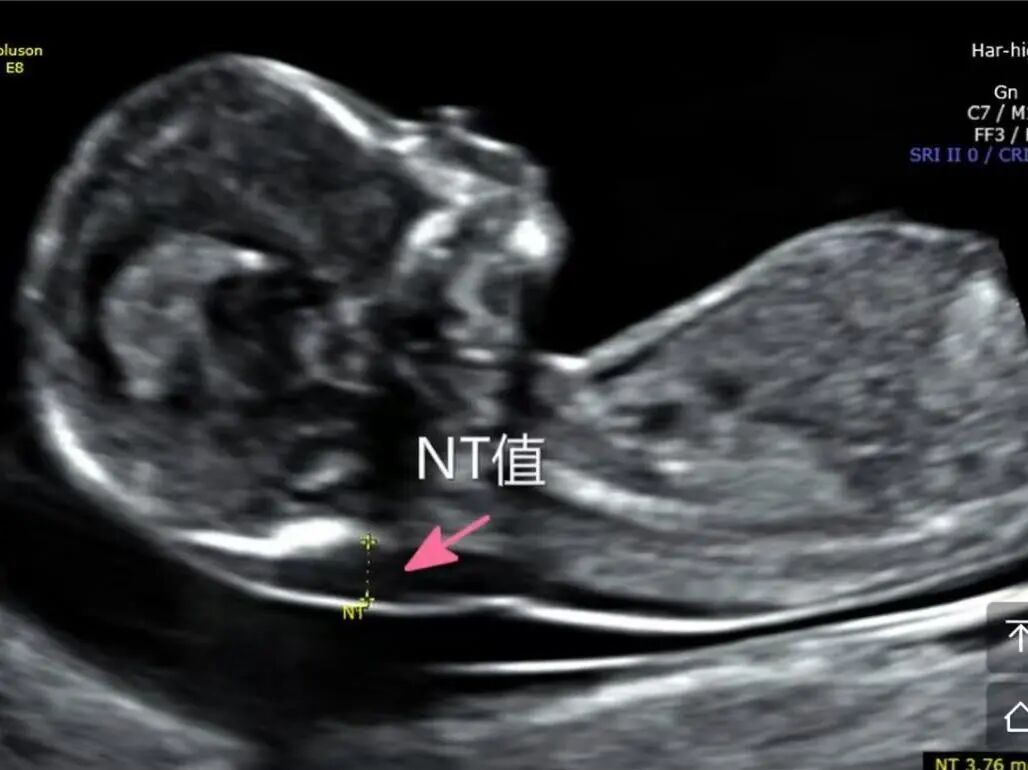

1月7日,贵州航天医院第91次晨读会由我院超声科医师杨向蓉作学术交流,她以“小微泡,大作用——右心声学造影”为题,详细讲解了右心声学造影的基本原理、适用情况、操作方式及心脏异常分流评估特点等内容,涵盖了该技术的实施条件、所用造影剂类型及多种激发试验方法,并通过多个病例图文资料分享了右心声学造影在相关症状病因探寻中的辅助角色,为临床评估提供了一种观察途径,有助于从循环角度了解某些症状的可能原因,在相应症状的病因分析中具有一定的参考意义。 贵州航天医院 超声科专家简介 吴艳辉 中共党员,超声科学科带头人,主任医师 专业擅长:从事超声诊断工作30余年,对心血管、小器官超声、超声引导下介入等具有丰富的临床经验。 胡大海 超声科主任,副主任医师 专业擅长:从事超声工作20余年,对心血管、外周血管、浅表器官、成人颅脑、超声造影诊断及超声引导下介入等具有丰富的临床经验。 骆科美 中共党员,超声科副主任医师 专业擅长:从事超声诊断工作30余年,对胎儿心脏及颅脑、妇产超声诊断、盆底超声等具有丰富的临床经验。 刘 敏 超声科副主任医师 专业擅长:从事超声诊断工作20余年,对妇产科超声、心脏血管超声诊断具有丰富的临床经验。 韩锡铁 超声科副主任医师 专业擅长:从事超声诊断近20年,对心血管、外周血管、浅表器官、肌骨神经超声诊断具有丰富的临床经验。 杨向蓉 中共党员,超声科主治医师 专业擅长:从事超声诊断工作16年,擅长心血管、浅表器官、盆底、腹直肌超声、右心声学造影及超声引导介入等技术。 贵州航天医院超声科简介 基本情况 贵州航天医院超声科配备多种超声检查设备(飞利浦彩超(IU-22、IU-Elite、EPIQ5、EPIQ7),迈瑞彩色超声(ResonaI9T、RechoR9、Resona I9、DC-8)、GE-VolusonE8、汕头SIUIAPogee6800、床旁彩色超声诊断仪等),设有心血管诊室、外周血管诊室、妇产科诊室、腹部诊室、绿色通道、浅表小器官等检查室。 诊疗范围 科室业务覆盖腹部、泌尿、妇科、产科(常规、NT筛查、系统筛查及高危妊娠监护)、成人心脏、外周血管、浅表器官(包含甲状腺、乳腺、阴囊、眼睛等)、颅脑(小儿颅脑、成人帕金森辅助筛查)、小儿肺超、超声造影、盆底、腹直肌、肌骨神经等检查及各种超声介入引导。 专科特色 四肢血管超声检查、产前系统筛查及超声监护、超声造影检查技术、介入超声临床应用、经颅脑实质超声辅助筛查诊断帕金森病、小儿髋关节筛查、女性性早熟超声诊断、盆底、腹直肌超声检查等。 NT超声检查 超声介入引导 肝脏超声造影 甲状腺造影 颅脑超声帕金森辅助检查 乳腺超声造影 上肢动静脉造瘘超声检查 双胎超声筛查 下肢血管超声检查 右心造影 end